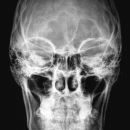

Schädel a.-p.

Fremdkörper-Lokalisation vor MRT, Shuntkontrolle

Rückenlage

Schädel liegt exakt gerade

Kinn anziehen bis Deutsche Horizontale senkrecht zur Bildebene

Symmetrische Abbildung beider Schädelhälften, Nasenscheidewand streng in der Mitte. Die Felsenbeine stellen sich im unteren bis mittleren Drittel der Orbita da. Felsbeinspitzen projizieren sich in die Mitte der Orbita oder eher etwas oberhalb davon.